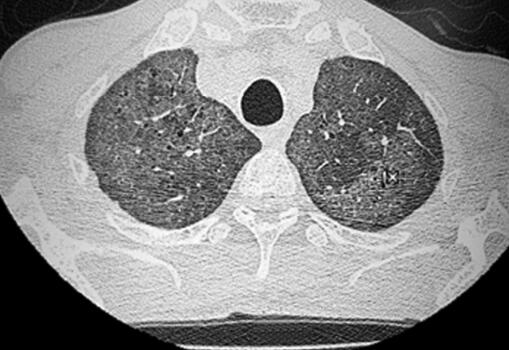

6.胸部HRCT:双肺多发磨玻璃影(如图3、图4)。

图3

2.肺部HRCT结果为弥漫性肺间质性改变,常见于巨细胞病毒性肺炎、过敏性肺炎、淋巴细胞间质性肺炎、肺泡蛋白沉积症等,但①患者无过敏原接触史,血常规嗜酸性粒细胞正常,且过敏性肺炎发热少见,胸部CT多可见边缘模糊的小叶中央结节,此病例不符,可以除外过敏性肺炎;②淋巴细胞间质性肺炎胸部CT多可见弥漫性磨玻璃影伴薄壁囊腔、小叶中央结节,淋巴结增大,此病例不符,暂不考虑淋巴细胞间质性肺炎;③肺泡蛋白沉积症症状隐匿,高热和中毒缺氧不常见,且胸部HRCT为磨玻璃影合并小叶间隔增厚(碎石路征),此病例不符,暂不考虑肺泡蛋白沉积症。目前不除外巨细胞病毒性肺炎。

3.动脉血气分析提示Ⅰ型呼吸衰竭,过度通气;结合血常规、痰病原学检查及胸部CT弥漫性磨玻璃影表现,进一步支持病原菌感染造成肺间质性炎症的诊断思路,目前病原菌尚不明确,且患者目前状态差,Ⅰ型呼吸衰竭,当前重要的是选择合适的药物进行经验性抗感染治疗,改善患者一般状态。